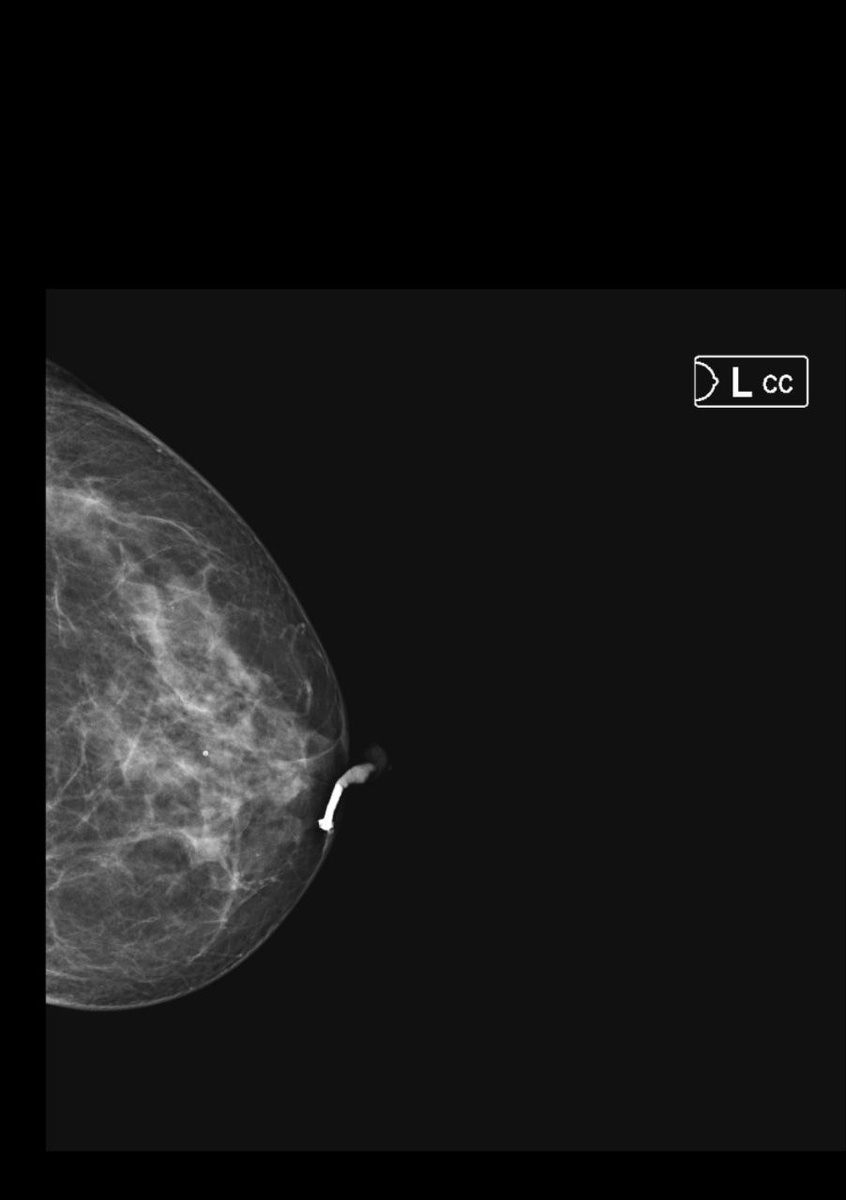

Классическая клиническая картина внутрипротоковой папилломы - обильный выделения из соска соломенного цвета.

На дуктограммах левой молочной железы на границе внутренних квадрантов (близко прилегает к коже) определяется неравномерно заполненный контрастированный магистральный млечный проток, балонно расширенный проток.

Начиная с подсосковой зоны на расстоянии 0,9см, бифурация протока, далее "обрыв" протока - контрастный препарат не определяется, вероятнее за счет внутрипротокового компонента размером от 0,13см в трех ветвях.

Лечение хирургическое в объёме секторальной резекции.